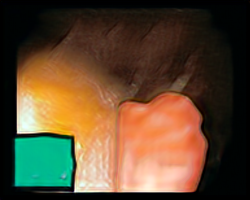

A few sample images and the corresponding masks of the polyp dataset in HyperKvasir are shown in Fig 2. The polyp images are RGB images. The masks of the polyp images are single-channel images with white () for true pixels, which represent polyp regions, and black () for false pixels, which represent clean colon or background regions. In this dataset, there are different sizes of polyps. The distribution of polyp sizes as a percentage of the full image size is presented in the histogram plot in Fig 3, and we can observe that there are more relatively small polyps compared to larger polyps. Additionally, a subset of this dataset was used to prove that the performance of segmentation models trained with small datasets can be improved using our SinGAN-Seg pipeline, and the whole dataset was used to show the effect of using SinGAN-Seg generated synthetic images instead of a large dataset which has enough data to train segmentation models. In this regard, this dataset was used for two purposes:

After training SinGAN-Seg models, we generated random samples per real image using the input scale , which is the lowest scale that uses a random noise input instead of a re-scaled input image. For more details about these scaling numbers and corresponding output behaviors, please refer to the vanilla SinGAN paper [56]. Three randomly selected training images and the corresponding first synthetic images generated using scale are depicted in Fig 4. The first column of the figure represents the real images and the ground truth mask annotated from experts. The rest of the columns represent randomly generated synthetic images and the corresponding generated mask.